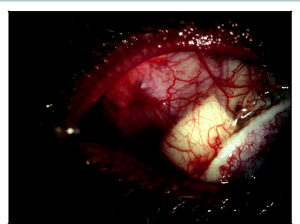

Glaucoma drainage implants are effective at controlling pressure in aniridic glaucoma. Molteno implants were effective at controlling pres-sure in 5 (83%) out of 6 eyes in a series by Wiggens and Tomey.[4] Similarly, Baerveldt glaucoma drainage implants have been shown to control IOP in aniridic glaucoma.[5] Success with Ahmed valves in aniridia patients with glaucoma has also been demonstrated, but some patients required needling and 5-fluorouracil.[6] Glaucoma drainage implants have been the treatment of choice in my practice for older patients with aniridia, and I have been very satisfied with the level of pressure control achieved with these techniques (Figure 1A and B). The surgeon has to be prepared to manage surface-related complications such as tube erosions, which may occur at a higher rate in patients with severe surface disease and stem cell deficiency (Figure 2).

In our practice, when patients require 2 to 3 topical medicines preoperatively to control their glaucoma, we generally recommend glaucoma drainage implant surgery prior to undergoing keratolimbal allograft surgery. In general, the glaucoma worsens following the keratolimbal allograft surgery, and it is desirable to minimize topical glaucoma medicines following the stem cell transplant. It is also possible to place a tube shunt follow-ing keratolimbal allograft surgery. Careful attention needs to be taken to preserve the keratolimbal allograft integrity during the tube shunt insertion (Figure 3).

Tube insertion in a keratolimbal allograft patient starts by creating a conjunctival peritomy at the posterior lip of the keratolimbal allograft for approximately 100 degrees. The glaucoma drainage implant plate is placed in a routine fashion and secured to the sclera. A dissection is carried out between the sclera and keratolimbal allograft segment. Usually, this is fairly easy because there is already a plane between the keratolimbal allograft lenticule and the sclera. The segment of the keratolimbal allograft is then elevated, a 23-gauge needle is used to make an entry into the anterior chamber 1.5 mm posterior to the limbus, and the tube is inserted into the eye. After the tube is at the desired length and positioned in the anterior chamber, the keratolimbal allograft is then placed back in its original position and secured to the sclera with interrupted 10-0 nylon sutures. A small tissue patch graft is then placed behind the keratolimbal allograft segment, and the anterior portion of the tissue patch graft is positioned against and slightly posterior to the lip of the keratolimbal allograft to allow a small amount of “patch overlap.” This is done to ensure there is no gap in tube coverage by patch material (Figure 4). The conjunctival flap is closed by suturing the flap to the posterior lip of the keratolimbal allograft. I prefer a monofilament 9-0 Vicryl running suture on a Vas-100 needle.